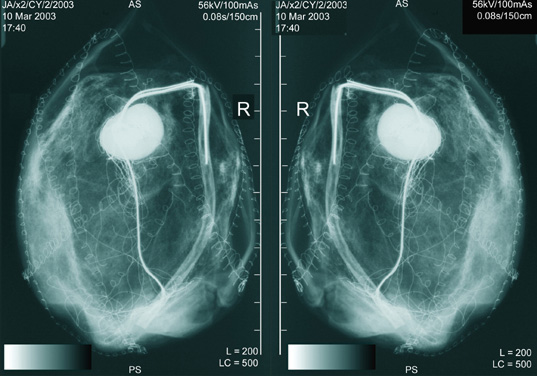

X-ray - Cyst 2